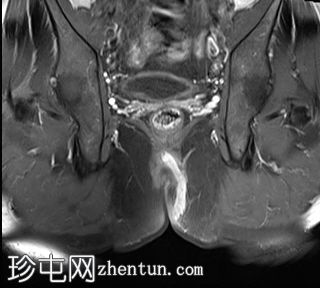

轴向位

T1时间

位于5点钟和6点钟位置之间,在STIR和T2加权图像上呈高信号。

瘘管起源于括约肌间平面附近,穿过肛门内外括约肌,并延伸至左侧坐骨肛门窝。瘘管内充满液体信号,周围有轻微水肿。肛提肌上方未观察到颅骨延伸。

根据圣詹姆斯大学医院的磁共振分类系统,该病例被归类为III级左侧肛周经括约肌瘘,左侧坐骨肛门窝可见炎症改变。